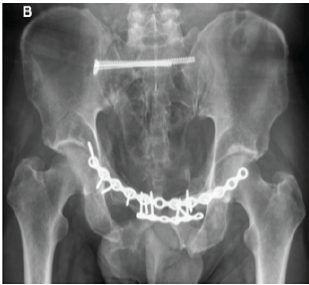

Intraoperative Diagnosis and Management of Testicular Dislocation During Pelvic Fracture Fixation: A Report of Two Cases and Literature Review

Aleix Agelet-Pueyo , Ona Ibáñez-Zurita , Alfred Llop-Corbacho , Karla Bascones-Rodriguez , Carles Tramunt-Monsonet

………………………………p.188-192